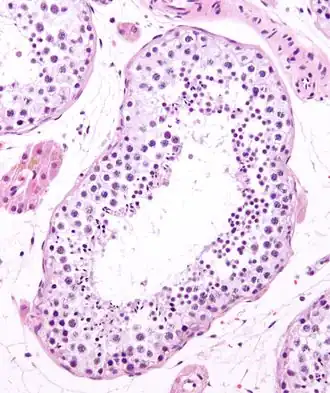

Seminiferous tubule in cross-section (large tubular structure – center of image) with sperm (black, tiny, ovoid bodies furthest from the outer edge of the tubular structure). H&E stain.

Seminiferous tubules (Latin for "seed-bearing small tubes") are located within the testicles, and are the specific location of meiosis, and the subsequent creation of male gametes, namely spermatozoa.

The epithelium of the tubule consists of a type of sustentacular cells known as Sertoli cells, which are tall, columnar type cells that line the tubule.

In between the Sertoli cells are spermatogenic cells, which differentiate through meiosis to sperm cells. Sertoli cells function to nourish the developing sperm cells. They secrete androgen-binding protein, a binding protein which increases the concentration of testosterone.